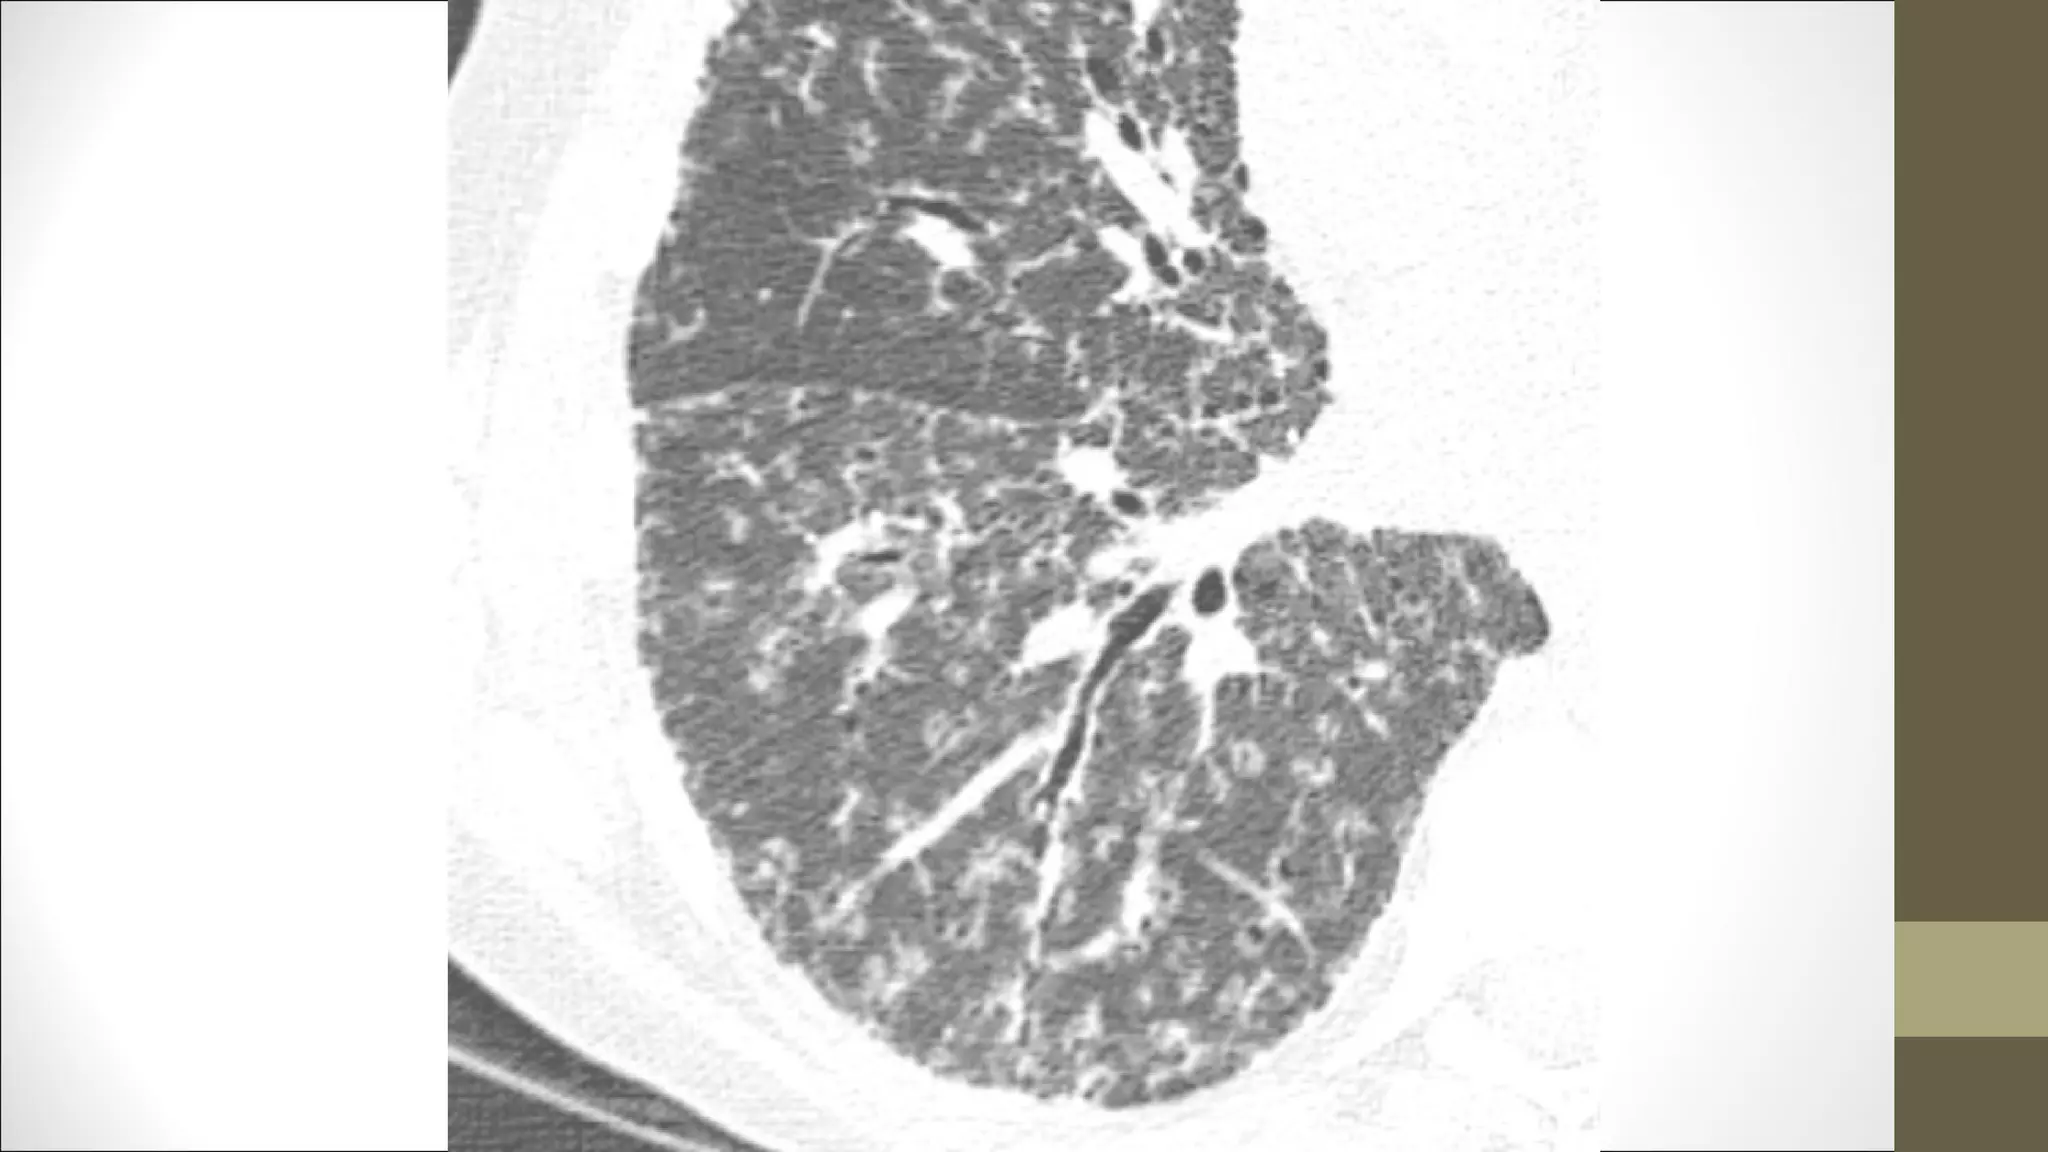

Sarcoidoza

CT